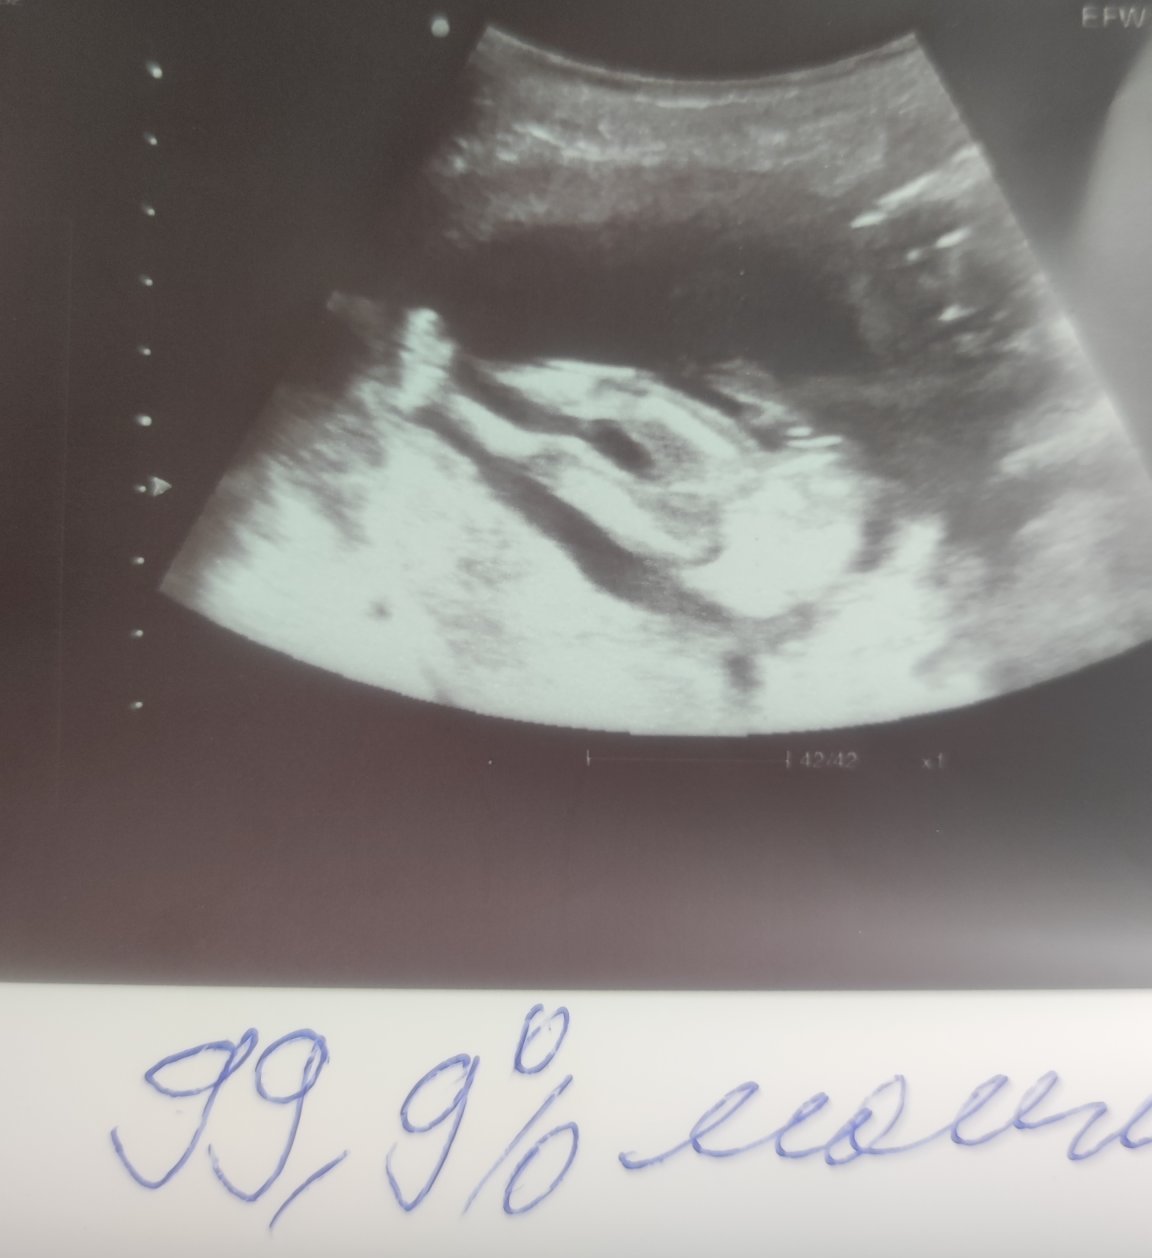

Здравейте февруарски мами!!❤️ Днес ми беше прегледа и очакваме 99.9% момиченце🩷🩷🩷🥳 много съм щастлива👣🥰 Видяха се срамни устни и малката си застана точно за да и направим една фотосесия между крачетата 😁🌼🌼🌼